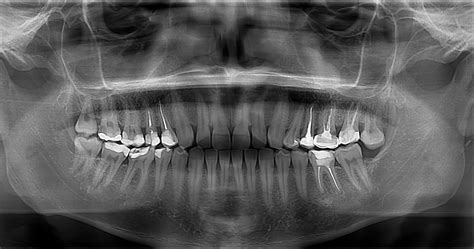

Una de las grandes particularidades de un quiste oral es que no duele y por eso en muchas ocasiones pasa desapercibido para el paciente. Generalmente es necesario realizar una radiografía para diagnosticar esta patología que se manifiesta a través de una zona oscura en el hueso. A pesar que su crecimiento sea lento, es muy recomendable para evitar que alcancen un gran tamaño.

- Quiste Dentígero (o folicular) (QD): Dicho quiste aparece como una lesión unilocular, radiolúcida, bien definida y asintomática (excepto cuando alcanza un tamaño considerable). Se asocia a la corona de dientes no erupcionados y clínicamente puede expandir el hueso cortical hasta tal punto que provoca el desplazamiento de los gérmenes y la reabsorción radicular de los dientes adyacentes.

El diagnóstico se basa en los hallazgos radiológicos e histológicos. Una adecuada exploración clínica y radiográfica por parte del odontólogo es suficiente para alcanzar un diagnóstico de presunción. El diagnóstico definitivo lo dictaminará el análisis anatomopatológico.